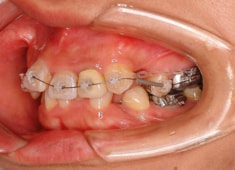

治療開始時

治療開始から1年8ヶ月後